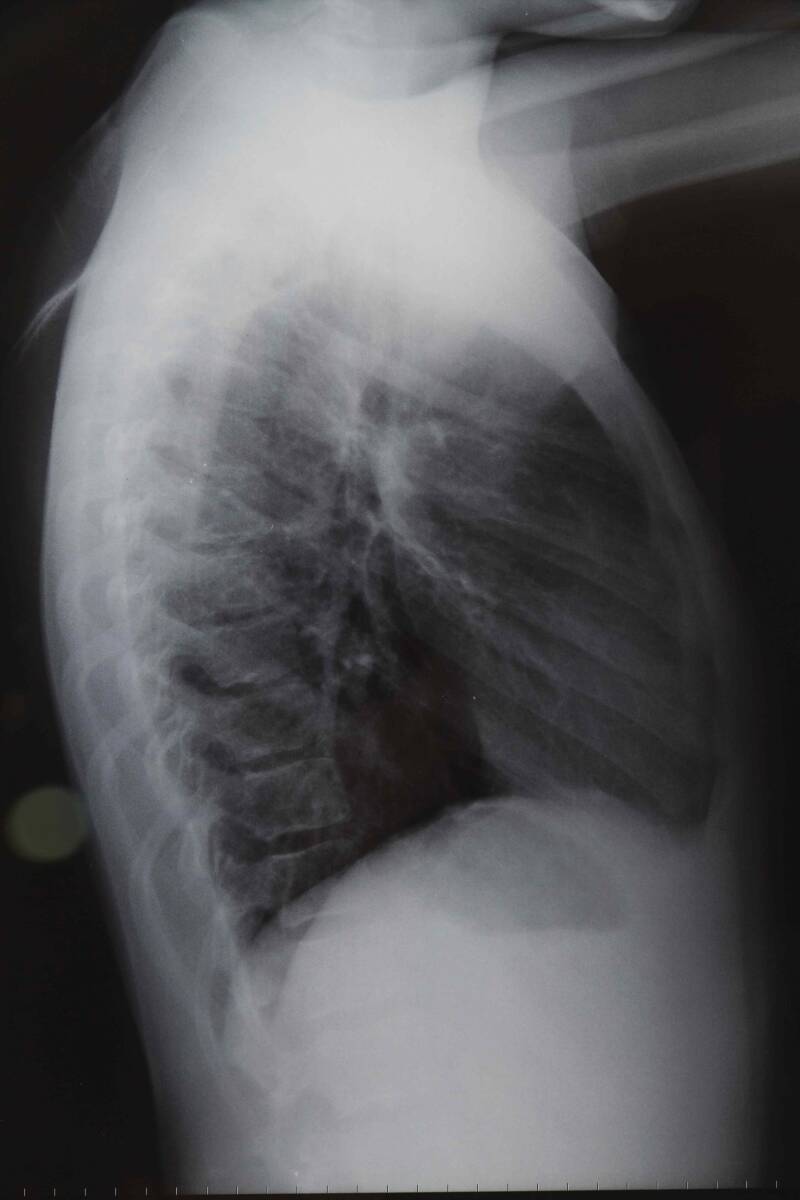

Lungenfibrose

Lungenfibrose ist eine progressive Lungenerkrankung, die durch eine übermäßige Ansammlung von Bindegewebe in den Lungen gekennzeichnet ist. Dies führt zu einer Versteifung der Lungen und einer Einschränkung der Atmungsfunktion.